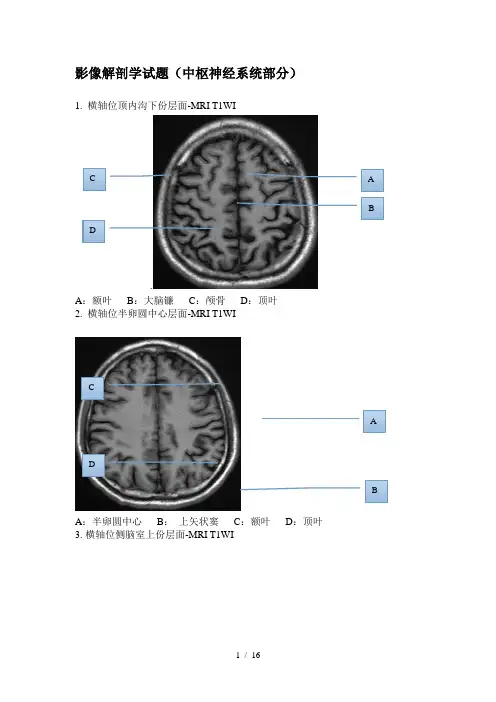

影像解剖学试题(中枢神经系统部分)1. 横轴位顶内沟下份层面-MRI T1WI.A :额叶B :大脑镰C :颅骨D :顶叶 2. 横轴位半卵圆中心层面-MRI T1WIA :半卵圆中心B : 上矢状窦C :额叶D :顶叶 3. 横轴位侧脑室上份层面-MRI T1WIA BDC ABDCA:侧脑室体部B:大脑镰C:透明隔D:顶叶白质4. 横轴位侧脑室中份层面-MRI T1WIA:胼胝体膝部B:尾状核头C:侧脑室前角D:背侧丘脑5.横轴位侧脑室中份层面-MRI T1WI BCA DADB CA :透明隔B :胼胝体压部C :内囊前肢D :内囊后肢E :枕叶 6.横轴位侧脑室下层面-MRI T1WIA :穹窿B :屏状核C :壳核D :苍白球 7. 横轴位侧脑室下层面-MRI T1WIABEDCCADBA:颞叶 B:侧脑室三角区 C:外侧裂池 D:松果体8. 横轴位侧脑室下层面-MRI T1WIA:室间孔 B:枕叶 C:外囊 D:岛叶9. 横轴位第三脑室层面-MRI T1WI B ACCDCCCDCABA:外侧裂池 B:前联合 C:第三脑室 D:侧脑室三角区10. 横轴位第三脑室层面-MRI T1WIA:丘脑 B:大脑大静脉池 C:尾状核 D:枕叶11.横轴位中脑上份层面-MRI T1WI AD C BC CC CD C B AA:上丘脑 B:侧脑室枕角 C:四叠体池 D:小脑蚓部12.横轴位中脑中份层面-MRI T1WIA:额叶直回 B:环池 C:脚间池 D:中脑导水管13.横轴位中脑中份层面-MRI T1WI B ACCDCA CCB DCA :海马钩回B :鞍上池C :大脑脚D :四叠体池 14.横轴位中脑下份层面-MRI T1WIA :鞍上池B :侧脑室颞角C :眼球玻璃体 D:球后脂肪间隙 15.横轴位桥脑上份层面-MRI T1WIAC CBD CABC CD CA :垂体B :第四脑室C :桥脑D :小脑半球 16.横轴位桥脑中份层面-MRI T1WIA :筛窦B :海绵窦C :颈内动脉海绵窦段D :第四脑室 17.横轴位延髓层面-MRI T1WIBD CAC C ABD CC CA :鼻中隔B :延髓C :乳突小房D :枕骨粗隆 18. 矢状位椎管层-MRI T2WIA :脊髓B :脊髓圆锥C :马尾D :椎体E :蛛网膜下腔F :椎间盘19. 冠状位垂体层面-MRI T1WIBAC CD CAEBCD CFA:视交叉 B:垂体柄 C:垂体 D:第三脑室20.正中矢状位-MRI-T1WIA:中脑 B:脑桥 C 延髓 D:胼胝体 E:垂体21. 横轴位头颅基底节层面-CT AC D BDBE D C AD DA:尾状核 B:豆状核 C:丘脑D:内囊前肢 E:内囊膝部 F:内囊后肢22.横轴位颅底层面-CTA:圆孔 B:卵圆孔 C:棘孔D:翼腭窝 E:破裂孔ADDB EDC FDAE B CD DA:翼突外侧板 B:枕骨大孔 C:翼突内侧板23. 颅内动脉DSA正侧位ACBA :大脑中动脉B :大脑后动脉C :基底动脉D :椎动脉A :大脑前动脉B :大脑中动脉C :颈内动脉C5段D :颈内动脉C4段E :颈内动脉C3段24. 颅内动脉CTA 正侧位ACBDABCDEA :大脑前动脉B :大脑中动脉C :大脑后动脉D :颈内动脉A :大脑中动脉B :大脑后动脉C :大脑前动脉D :颈内动脉25. 头颅MRA 正侧位BDACABCDA :大脑前动脉B :大脑中动脉C :大脑后动脉D :颈内动脉A :大脑中动脉B :大脑后动脉C :大脑前动脉D :颈内动脉26. 头颅MRV 正侧位A :上矢状窦B :横窦C :乙状窦BCADABCDACBACB DA:上矢状窦 B:直窦 C:下矢状窦 D:大脑大静脉。